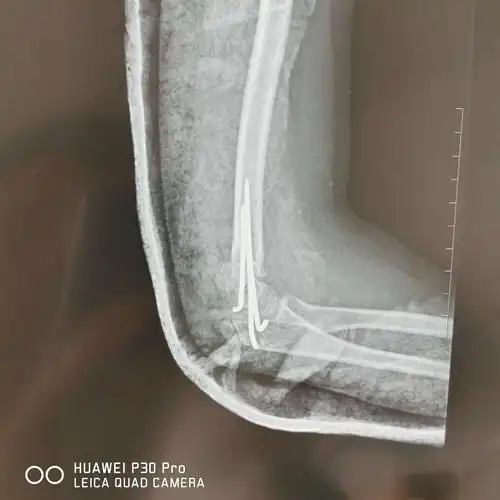

儿童肱骨髁上骨折gartland4型

肱骨髁上骨折

桡a搏动弱,手指触觉减退,伸拇肌力m4;诊断"肱骨髁上骨折 伸直桡偏型